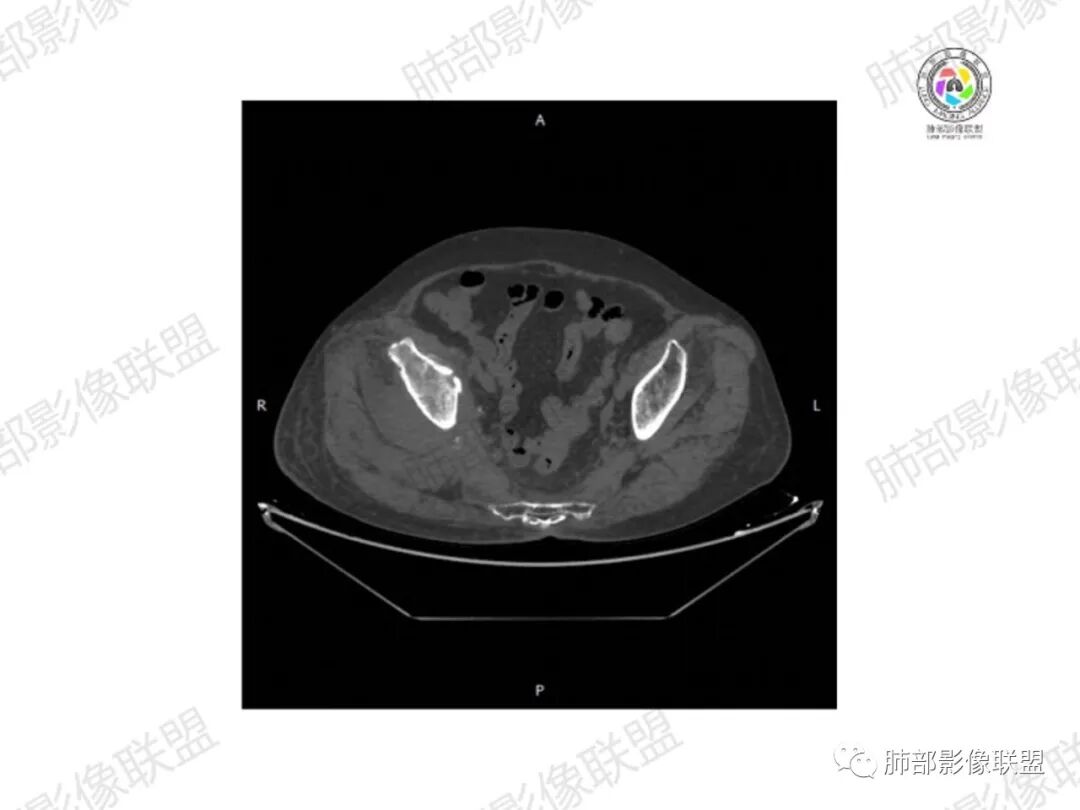

1.老年女性,直肠癌术后放疗后5年,右臀部疼痛4个月,加重半月

2.右髂骨轻度变形伴广泛骨质吸收破坏,边界不清且突破骨皮质。近中线区以溶骨性破坏为主,髂骨翼一侧则成骨性改变明显,骨表面见垂直骨针或花边样高密度瘤骨。

3.患骨多处皮质断裂,符合病理性骨折。注意折端可能会形成骨痂,但本例无论是形态还是部位都不符合骨痂。

4.患骨两旁(即盆骨内外)见边界不清的较大范围软组织快影,其间偶见骨化影。

5.双肺多发类圆形结节影,边界清楚,随机分布,其间多见钙化密度影。

6.双肺门及纵隔未见肿大淋巴结。

1.边界不清的骨质吸收破坏,溶骨明显,骨皮质突破,软组织肿块,种种迹象表明其恶性无疑!

2.但注意这是有“成骨”的恶性骨肿瘤!我们知道老年患者的骨原发性恶性肿瘤“成骨”非常少见。少数转移瘤可为成骨型或混合型,女性患者如乳腺癌骨转移等。在男性,最典型的成骨转移是前列腺癌。

本例右侧髂骨具有较为典型的“骨肉瘤”影像学特征,有边界不清的吸收破坏、有新生骨、形成软组织肿块等等。

3.双肺病灶符合转移瘤,伴有中央部分钙化者也以骨肉瘤转移较为多见。